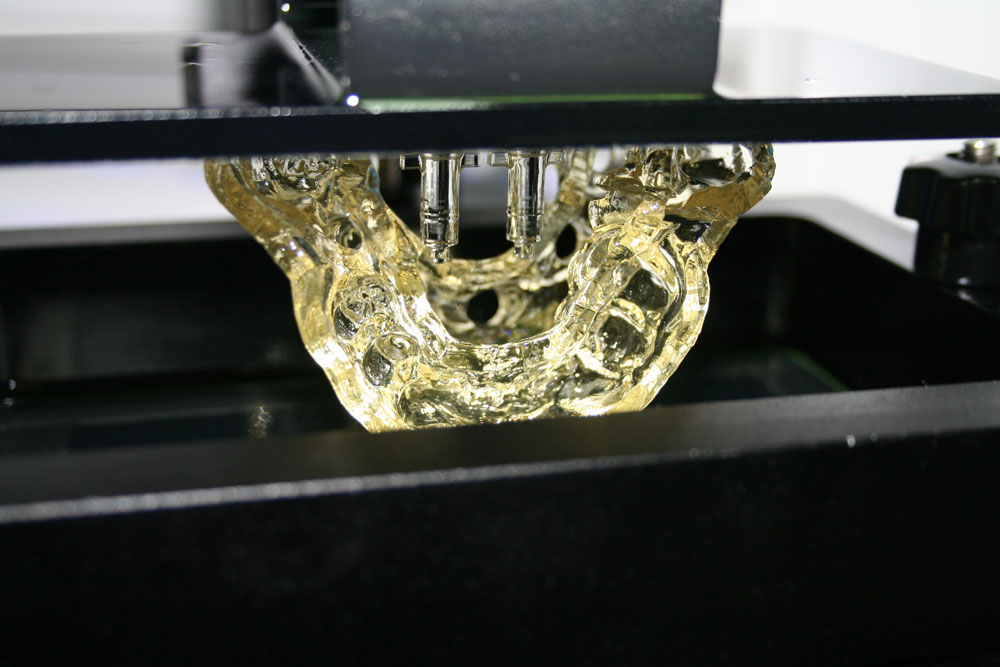

Мы печатаем хирургический шаблон на нашем 3D-принтере и применяем исключительно биосовместимые материалы. Процесс печати шаблона занимает около двух часов, после чего шаблон проходит этап стерилизации. Далее наступает время самой операции. Имплантация проходит под местной анестезией и занимает от 15-ти минут до 1-ого часа, в зависимости от количества зубных имплантатов. Хирургический шаблон исключает любые ошибки и погрешности: имплантаты будут устоновлены именно так, как врач их расставил на виртуальной 3Д-модели в компьютере, с точностью до 5-ти микрон. Мы обеспечиваем наивысший уровень безопасности наших пациентов с помощью инновационных 3D-технологий!